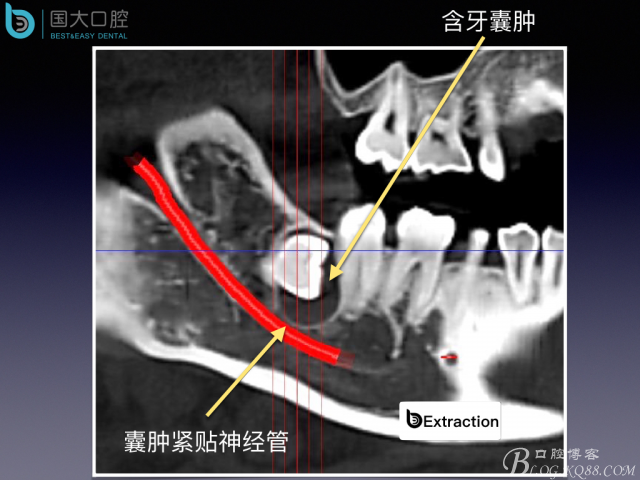

高難度阻生牙的拔除術(shù)設(shè)計